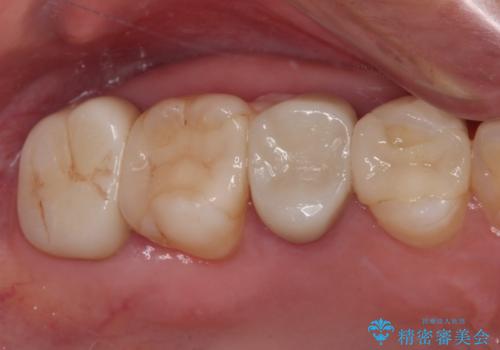

- 見た目の不揃いなセラミックと、痛みを感じる歯を気にして来院された患者様です。

痛みが引いた後、不揃いな見た目で気になっていた左下の奥歯とともにオールセラミッククラウンにて補綴治療を行うこととしました。